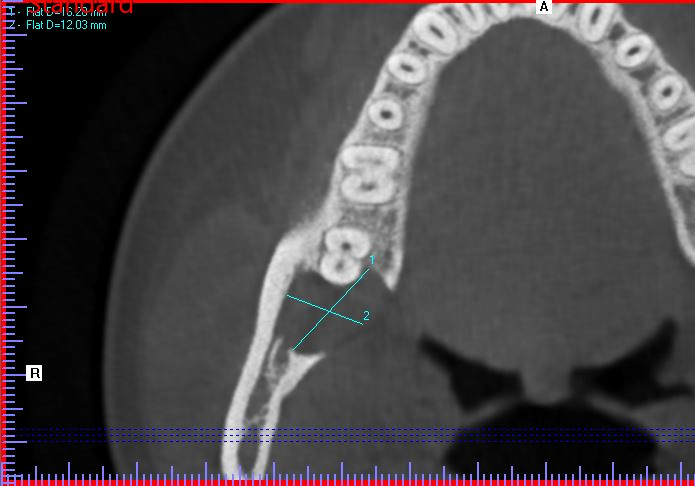

A 19-year-old female presented with a one-week history of pain and swelling in the right mandibular quadrant. Her Medical and Dental History were unremarkable. On clinical exam, the ginigva in the area of the right retromolar pad was erythematous and tender to palpation. On radiographic exam, a well-circumscribed, regular-bordered radiolucency was noted 18mmx15mm in its greatest dimension. Tooth #30 and #31 were vital on testing, and did not exhibit sensitivity to percussion. Probing depths distal to #31 were 2-3mm. Similar to case #1, the lingual cortical plate was violated and the roots of tooth #31 remained intact. After discussion of the risks, benefits and alternatives, she elected for excisional biopsy of the lesion under IV General Anesthesia. The surgery was undergone in a manner identical to Case #1, with the following exceptions: The Inferior Alveolar nerve and tooth roots of #31 were not largely involved with the lesion and therefore a peripheral ostectomy was feasible in all areas of the residual cavity. The patient was then closed in a double-layered fashion with resorbable suture material and allowed to recover from general anesthesia in the usual manner.